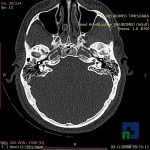

- Diagnosticul traumatismelor de bază de craniu

- Diagnosticul fracturilor:

-

- Unice

- Multiple

- Cu înfundare

- Complexe cranio-sinusale

- Complexe cranio-etmoidale

- Complexe cranio-orbitare

- Complexe cranio-faciale